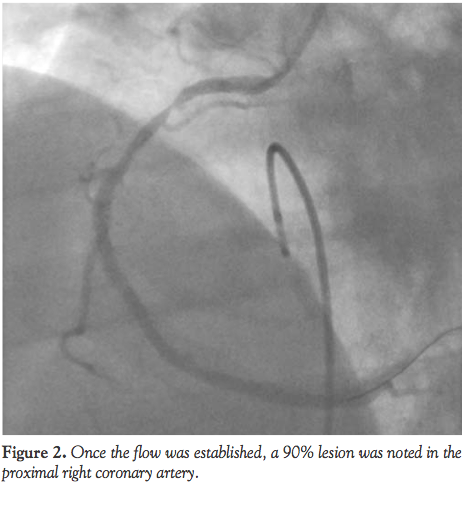

but because of hemodynamic instability and grave prognosis he was started on aspirin, heparin, and lidocaine drip and taken to the cardiac catheterization laboratory emergently. A transvenous pacemaker was placed. A Judkins Right 4 guide was used to engage the RCA, which was occluded proximally. Thrombus aspiration was done using a Pronto aspiration catheter (Vascular Solutions, Inc.). Once the flow was established, a 90% lesion was noted in the proximal RCA (Figure 2); this was predilated with a 3.0 x 15 mm Sprinter Legend balloon (Medtronic), then stented with a 3.5 x 15 mm Driver Rx stent (Medtronic) with optimal result and TIMI 3 flow (Figure 3). Angiogram of the left system revealed thrombus in the proximal LAD inside the previous LAD stent (Figure 4). The patient went into ventricular fibrillation again and was resuscitated according to Advanced Cardiac Life Support protocol. He was also started on eptifibatide due to a large amount of clot burden, hemodynamic instability, and concern for delay in effect of clopidogrel. Aspiration thrombectomy was performed in LAD with a Pronto aspiration catheter, and flow established in the LAD with some distal embolization. Predilatation of the lesion before and in the proximal part of the stent was done with a 3.5 x 12 Sprinter Legend balloon and this lesion was then stented with a 4 x 9 mm Driver Rx stent (Figure 5). An IABP was placed for hemodynamic support and due to recurrent ventricular tachycardia. He was started on clopidrogel and eptifibatide infusion was continued for 6 hours. Postcoronary intervention troponin peaked at 369 ng/mL and hemoglobin was stable at 12.6. There was worsening of renal function and elevation of liver enzymes secondary to cardiogenic shock. Transthoracic echocardiogram (TTE) revealed an ejection fraction of 30-35% with severe hypokinesia of septal, apical, and anterior walls. The patient continued to improve and was weaned off vasopressor support. Transvenous pacer was removed on postintervention day 3. INR was elevated at the range of 2.7 and he was given fresh frozen plasma and vitamin K before discontinuation of IABP. During this time, the patient had initially bloody then serosanginous drainage in the two JP drains, which was not unusually excessive. JP drains were removed on postoperative day 5. The patient had a prolonged hospitalization, but did not suffer any neurological damage and liver and renal functions returned to baseline. The patient continued to do well at 1 and 6 months after discharge. Repeat TTE done at 6 months showed improvement in wall motion abnormalities and ejection fraction of 45-50%.